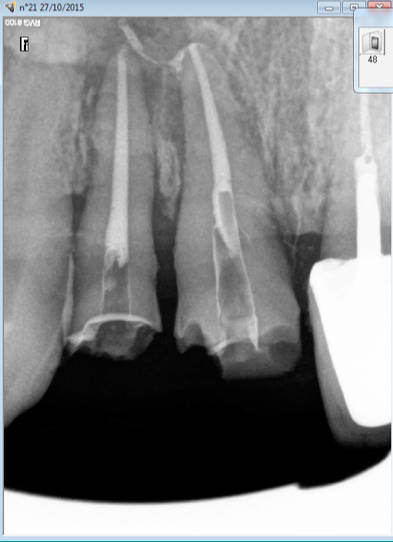

Endo taille empreinte provisoires 2H 30.

Gutta scellée au tubuli seal avec ou sans condensation thermo mécanique.

Logement du tenon réalisé au friendo ( voir photos) qui fond la gutta ( 200 ° au niveau de l'insert) . Un coup de machtou et hop tu peux passer les forets.

Avantage tu peux faire les provisoires et l'empreinte dans la séance et surtout tu peux raser les couronnes ce qui est un réel plus pour les endos surtout avec des pulpes rétractées comme ici ca évite de faire des conneries avec un abord palatin ou on ne voit rien du tout.